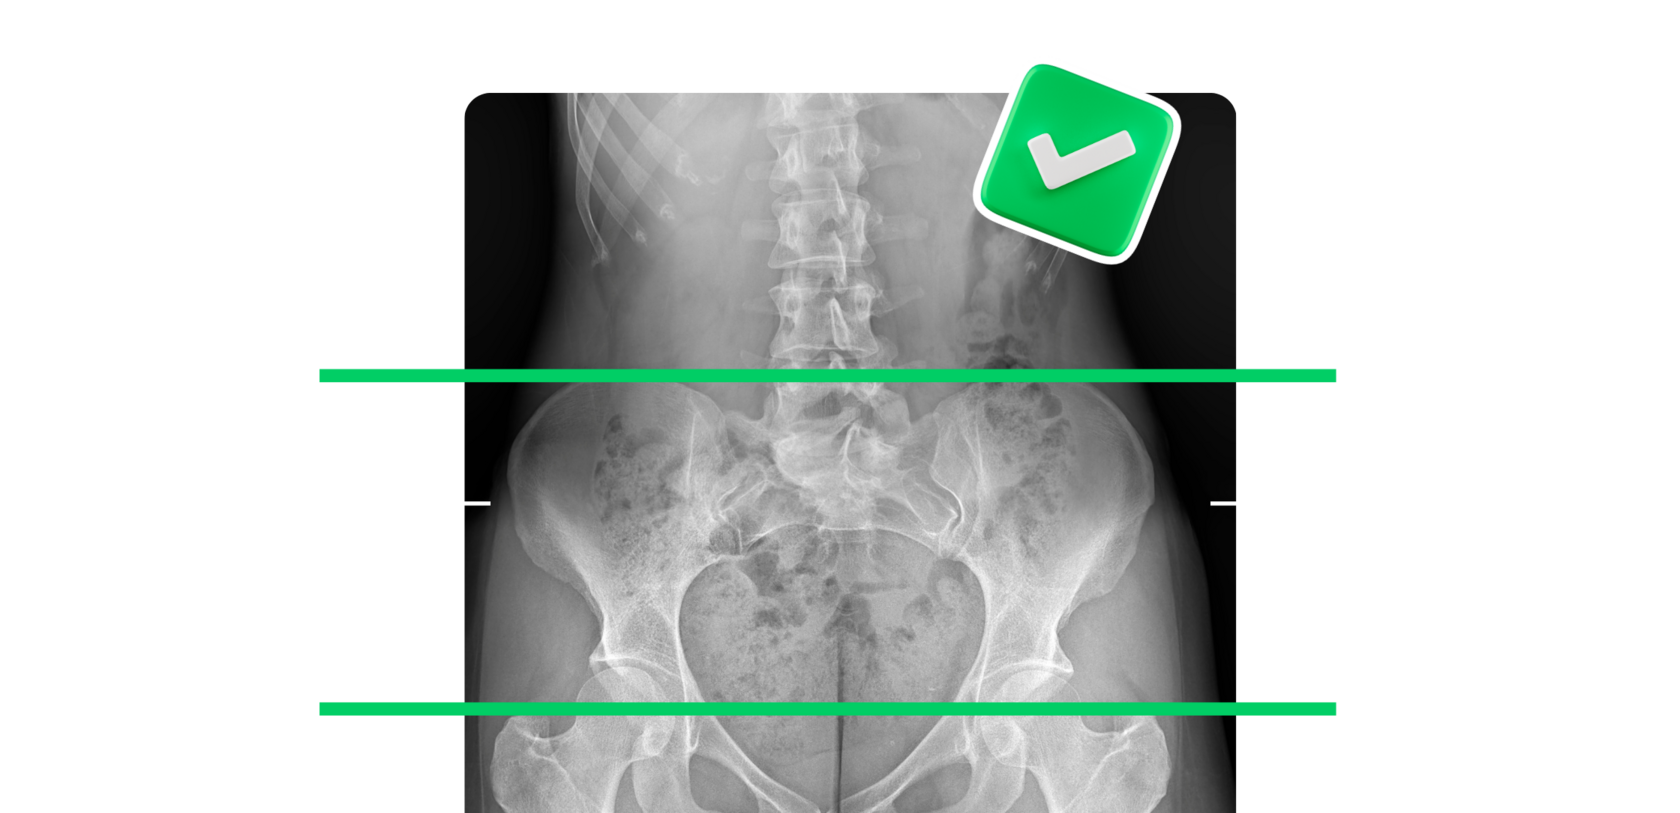

Речь о том, чтобы определить истинные причины перекоса таза, разобравшись в возможных триггерах и проведя рентгенологическое исследование костей таза и нижних конечностей. Это позволит вам понять, необходимо ли вам носить ортопедические стельки.

ПРИЧИНЫ ПЕРЕКОСА ТАЗА. КОГДА НУЖНЫ ОРТОПЕДИЧЕСКИЕ СТЕЛЬКИ

ДЗ: рентген-снимки и заключения "ДО"

ДЗ: рентген-снимки и заключения "ПОСЛЕ"